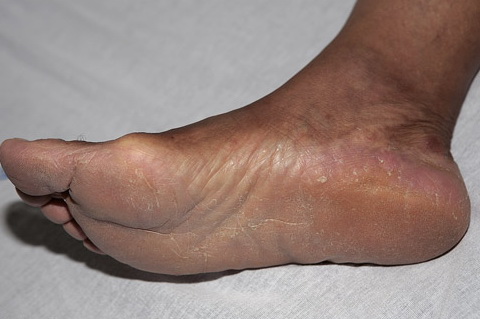

Chronic Hyperkeratotic Type.

Usually bilateral with patchy or diffuse scaling limited to the thick skin, soles, and the lateral and medial aspects of the feet, this is also known as “moccasin-type” tinea pedis. T. rubrum, the most common etiology, produces very few minute vesicles, leaving collarettes of scale less than 2 mm in diameter. Erythema is variable.